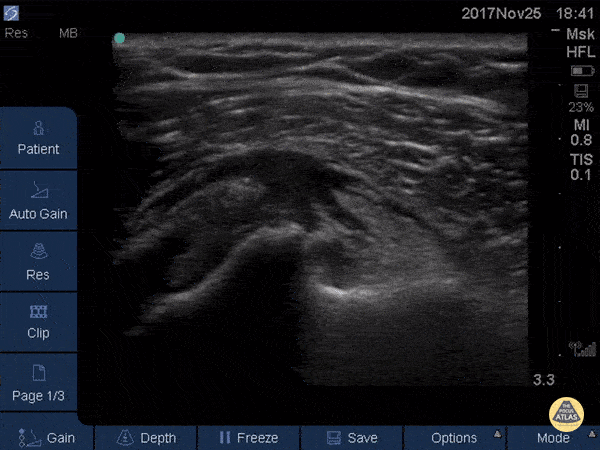

Musculoskeletal - Subscapularis Tendinopathy

50 year-old woman with anterior left shoulder pain; severe subscapularis tendinopathy with calcification and several small tears. Dr. Mike Butterfield